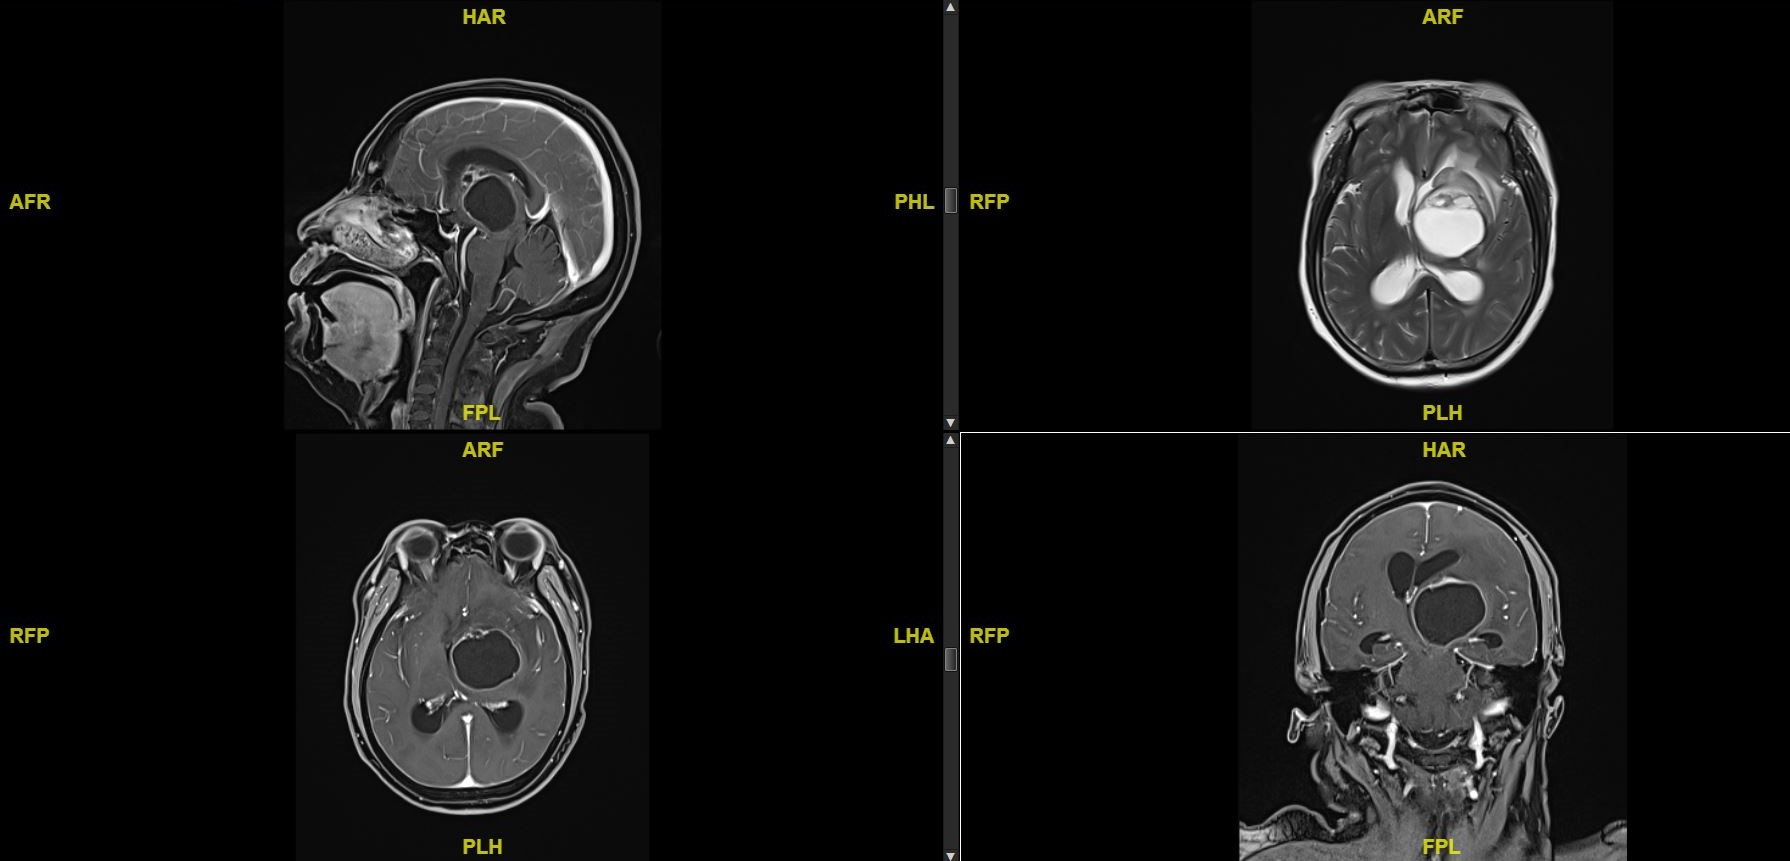

近1月来感头痛,我院MRI提示右侧枕叶结节此次不明显,左侧顶叶结节较前缩小,左基底节区巨大肿块,如下。

术前MRI,左侧基底节区巨大囊实性占位